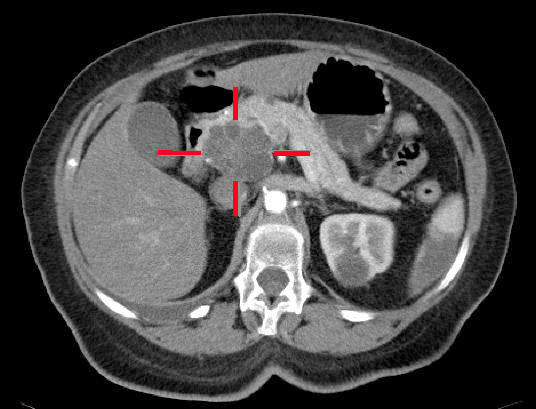

따라서 CA19-9는 단독 검사보다는 CT, MRI, 초음파, 내시경 검사 등과 함께 해석되는 보조 지표로 이해하는 것이 맞습니다.

사진 펼쳐보기 / 접기